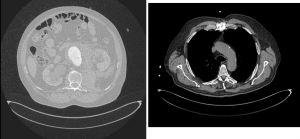

Efectivamente, esta imagen corresponde a una rotura de aneurisma de aorta abdominal ya que diferenciamos bien en el corte transversal una extravasación de contraste, hematoma retroperitoneal en el lado izquierdo y se realza la aorta y el trombo intramural en fase arterial.

Hallazgos compatibles con rotura aguda de aneurisma infrarrenal con hematoma retroperitoneal.